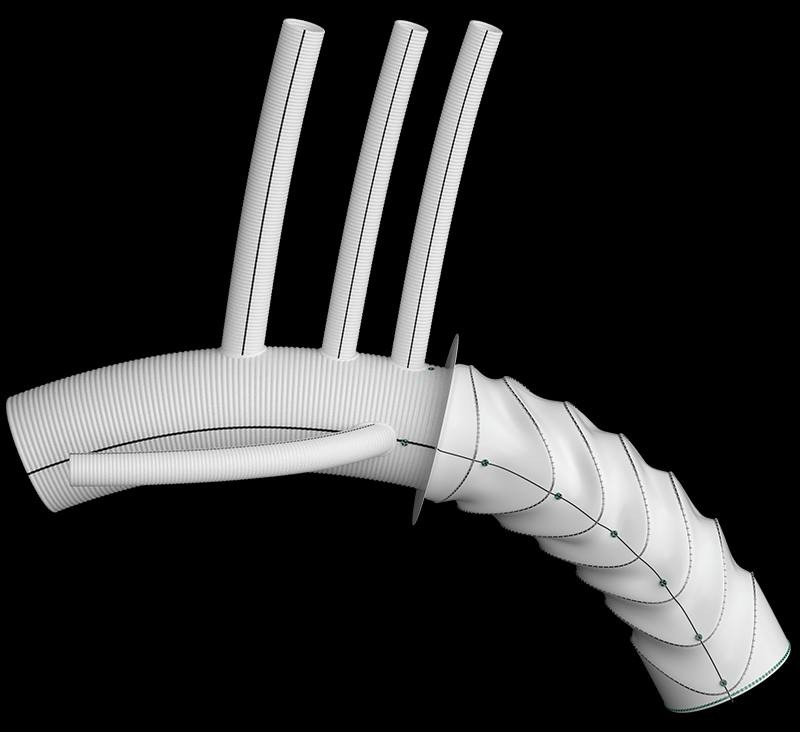

这是全球首款利用AI和AR技术的肺结节定位设备

项目类型

医疗器械区

起投金额

23000USDT

每日释放:0.82

释放周期:189 天

已购: 3913

剩余: 0